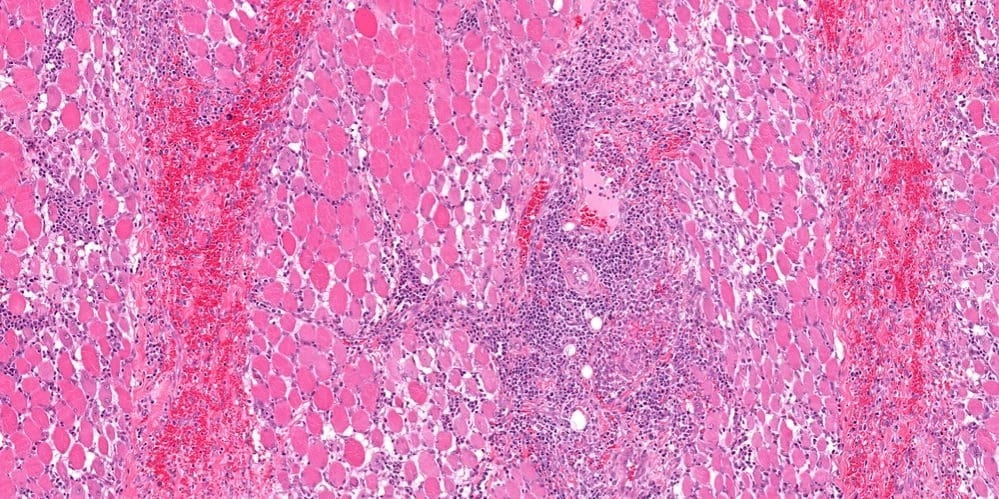

4. Миозит

Воспаление грудных мышц могут создавать ощущение, что болит сердце при вдохе.

Провоцируют мышечное воспаление:

Наиболее частая причина миозита: физическая работа в холодном помещении, когда вспотевший человек сильно переохлаждается.

Основное проявление: боль в сердце, усиливающаяся при вдохе или движении верхней конечности.

При надавливании на воспаленную мышцу происходит усиление болевых проявлений.

Если воспалительный процесс вызван патогенными микроорганизмами, то дополнительно появляется гипертермия и слабость.

При миозитах прописывают:

Если причиной стала бактериальная или вирусная инфекция, то назначаются медикаменты для уничтожения возбудителя.

При миозитах следует обратиться к хирургу.